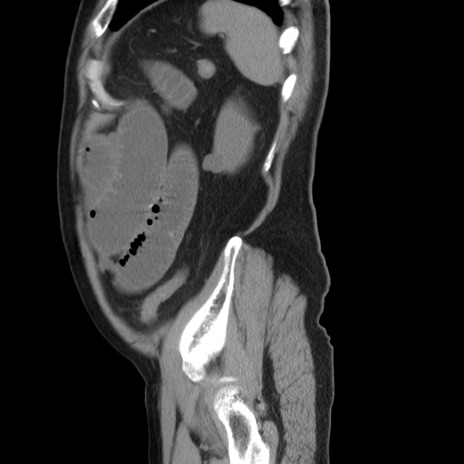

症例20(矢状断像)

【症例】 60歳代男性

【主訴】 腹部膨満、嘔吐

【現病歴】5日前頃より倦怠感を認め食事量減少し4日前の朝嘔吐、食事摂取困難となった。 3日前近医受診し点滴施行され整腸剤などを処方された。 当日他院を受診し、腹部膨満著明、炎症反応の上昇(CRP10.8、WBC11200)あり、紹介受診となる。

【身体所見】 意識JCS1 受け答えがはっきりしないBP 111/57mHg、 P 67bpm、、BT35.2°C、SpO2 97%(RA)、 腹部:膨隆、打診で鼓音あり、全体的に圧痛有り、腸蠕動音(-)、反跳痛ははっきりせず。

【データ】WBC 11400、CRP 14.20